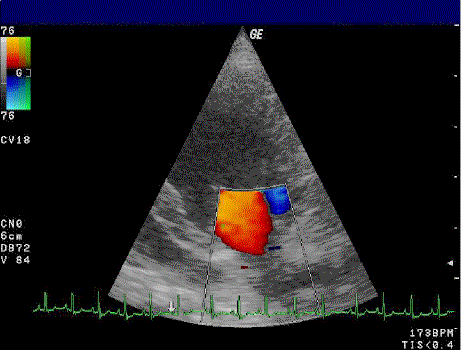

Color Doppler echocardiography test image showing blood flow velocities in the heart, with ECG trace, for Echocardiography Test in Bhopal.

It measures the direction and speed of blood flow within the heart. The Doppler Echocardiography Test in Bhopal helps identify blood leakage or valve blockage problems.